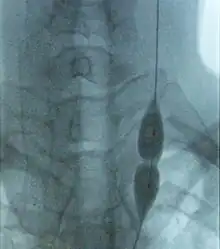

Balloon dilatation of stenosed jugular vein in a MS patient. Stenosis prevents the balloon from inflating (in the middle) while pressure is low.

Further trials are required to determine if the benefits, if any, of the procedure outweigh its risks.[21] Most experts, and medical and patients organizations, including the National Multiple Sclerosis Society of the USA or the Cardiovascular and Interventional Radiological Society of Europe (CIRSE), recommend not using the proposed treatment outside clinical trials until its effectiveness is confirmed by controlled studies.[3][5][7][21][37][38] Moreover, the CIRSE has stated that treatment research should begin by a small, placebo-controlled, prospective randomised trial which should be monitored by an independent organization.[38] An exception has been the Society of Interventional Radiology in the US and Canada, which considered research on the effectiveness of CCSVI intervention to be inconclusive as of 2010.[39] In March 2013 a press release indicated that the first prospective, placebo-controlled study of balloon angioplasty for MS had not shown any benefit of the therapy. The study, a phase II clinical trial designed to evaluate safety and efficacy of endovascular treatment, enrolled initially 10 patients that received the treatment and 20 more afterwards that were either allocated to receive angioplasty or a placebo intervention.[40]